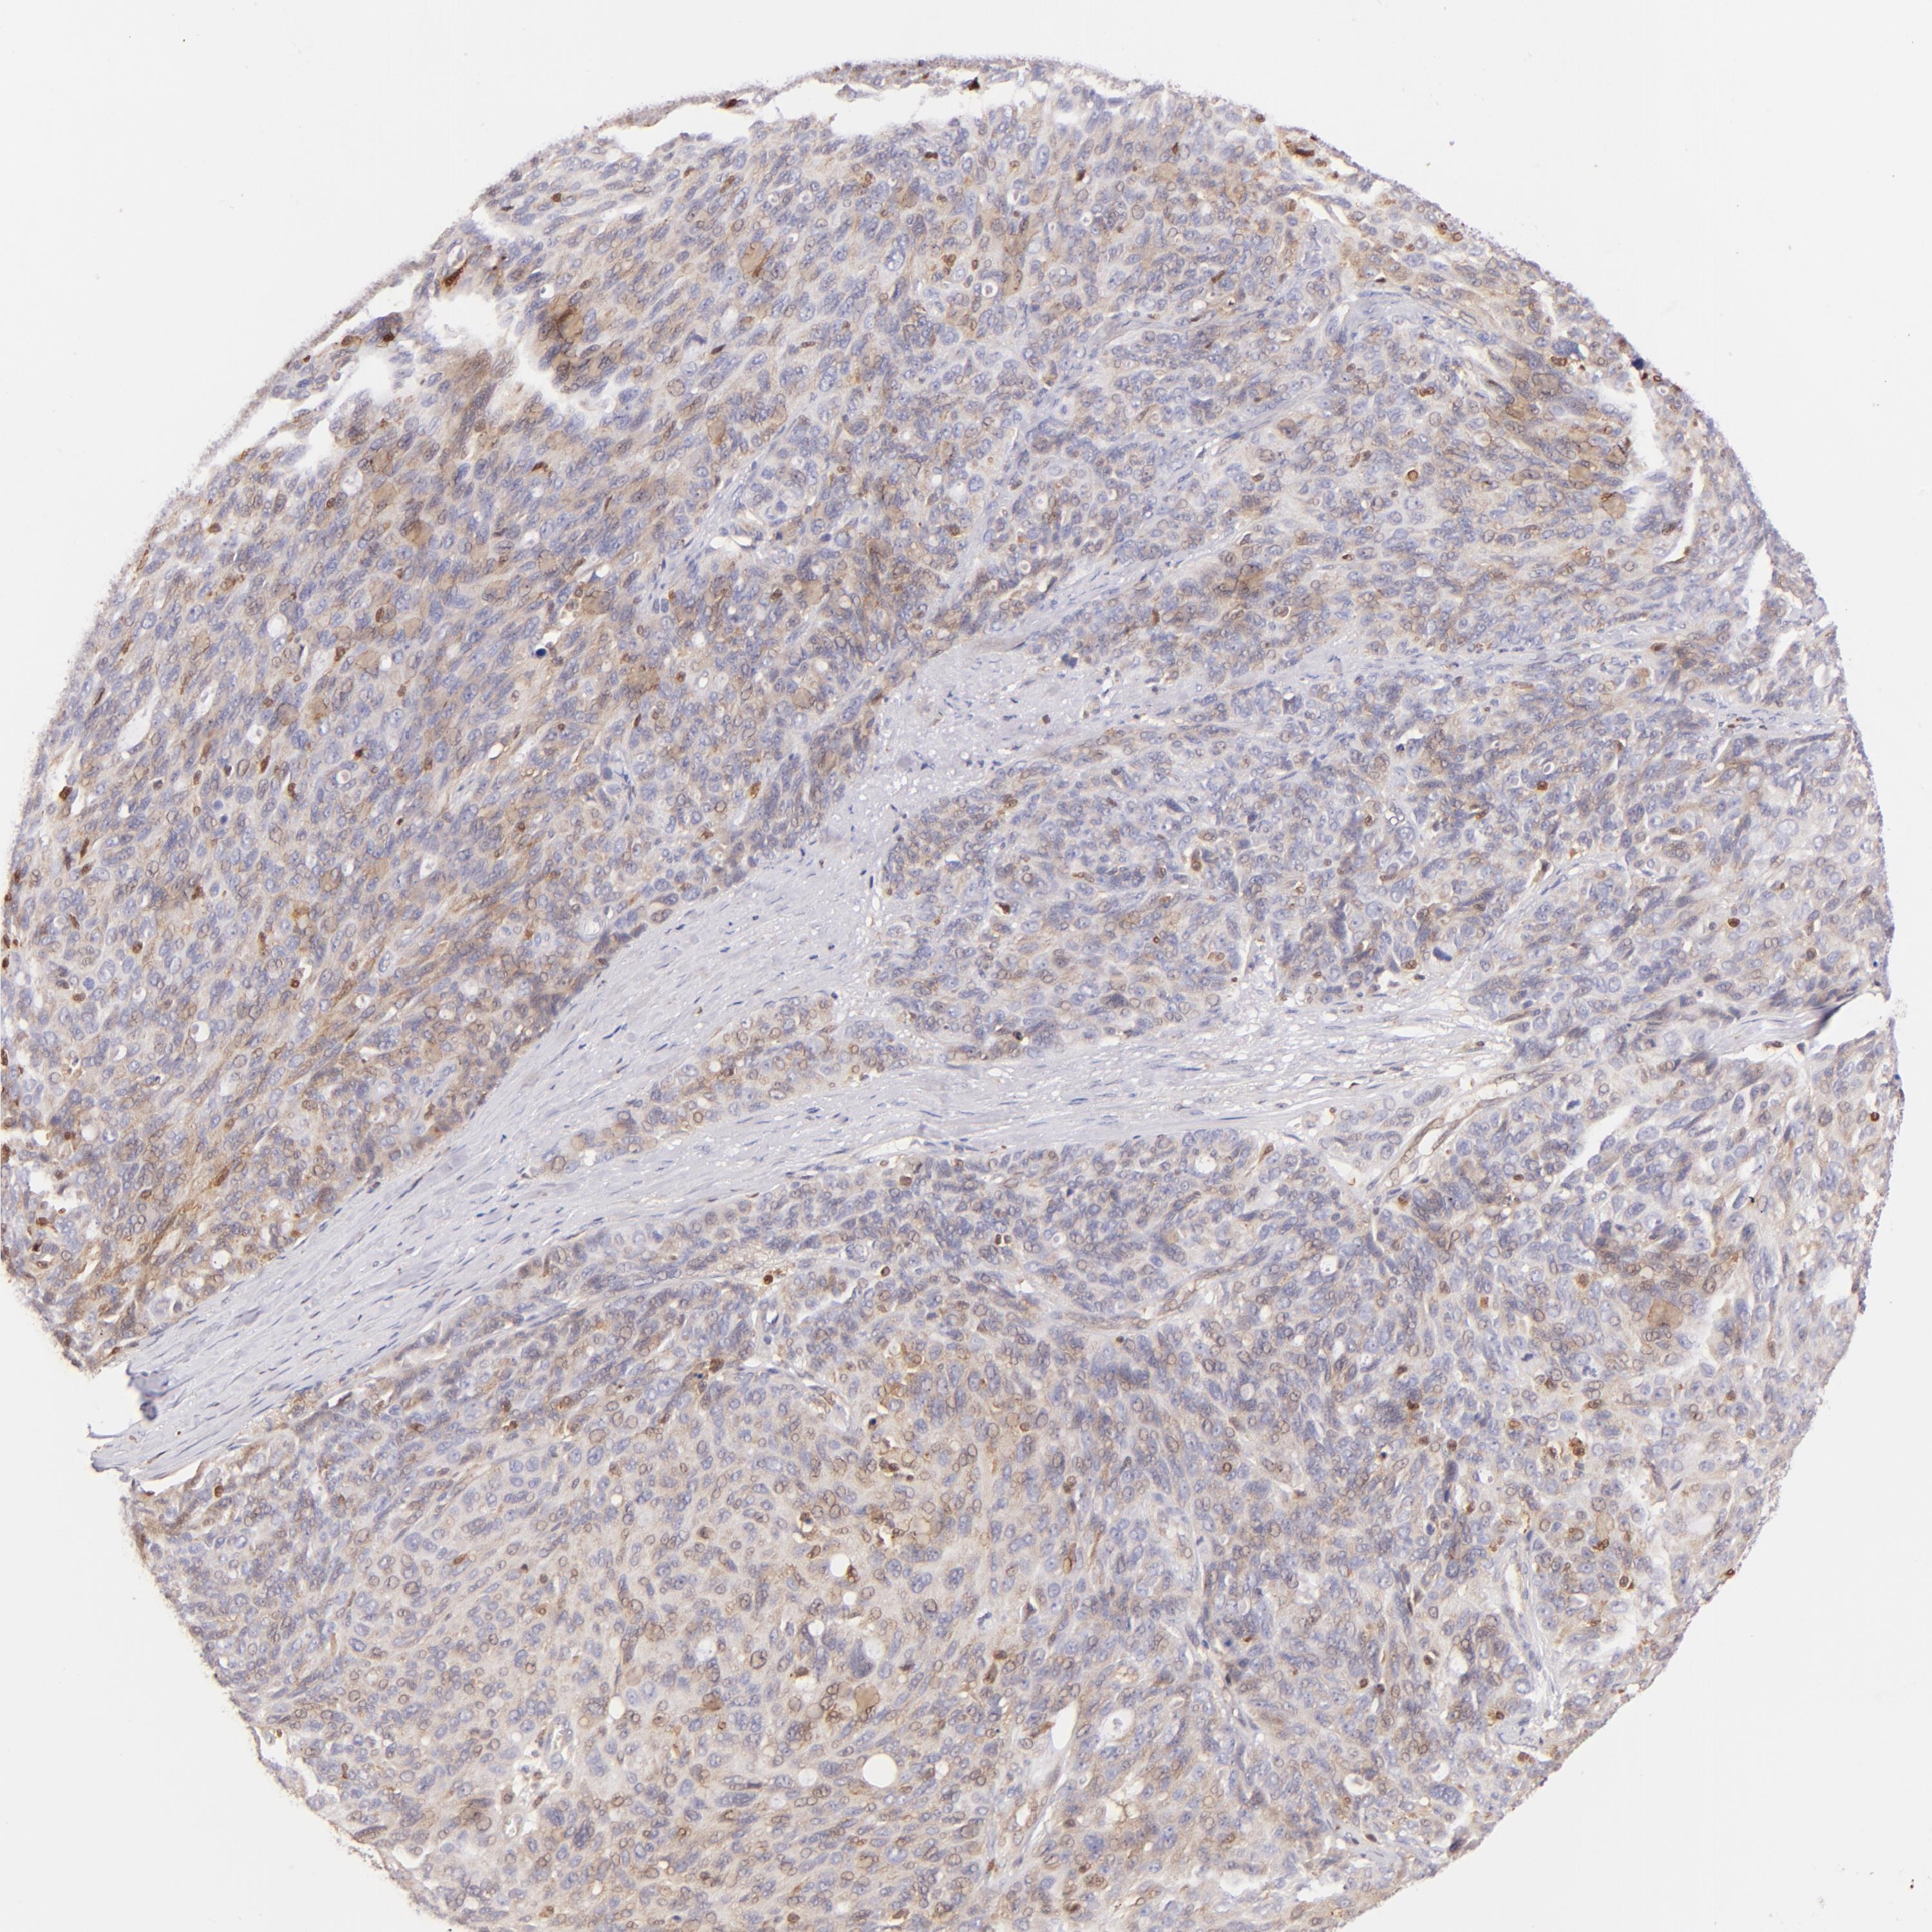

OVARIAN CANCER - Protein expressioni

A mouse-over function shows sample information and annotation data. Click on an image to view it in a full screen mode. Samples can be filtered based on level of antibody staining by selecting one or several of the following categories: high, medium, low and not detected. The assay and annotation is described here.

Note that samples used for immunohistochemistry by the Human Protein Atlas do not correspond to samples in the TCGA dataset.

Antibody stainingi

Antibody staining in the annotated cell types in the current human tissue is reported as not detected, low, medium, or high, based on conventional immunohistochemistry profiling in selected tissues. This score is based on the combination of the staining intensity and fraction of stained cells.

Each image is clickable and will lead to virtual microscopy that enables deeper exploration of all samples and also displays staining intensity scores, fraction scores and subcellular localization as well as patient and tissue information for each sample.

Antibody HPA001198

Antibody HPA002028

Antibody CAB016689

Antibody CAB080300

Cystadenocarcinoma, mucinous, NOS

Carcinoma, endometroid

Cystadenocarcinoma, serous, NOS

Carcinoma, NOS